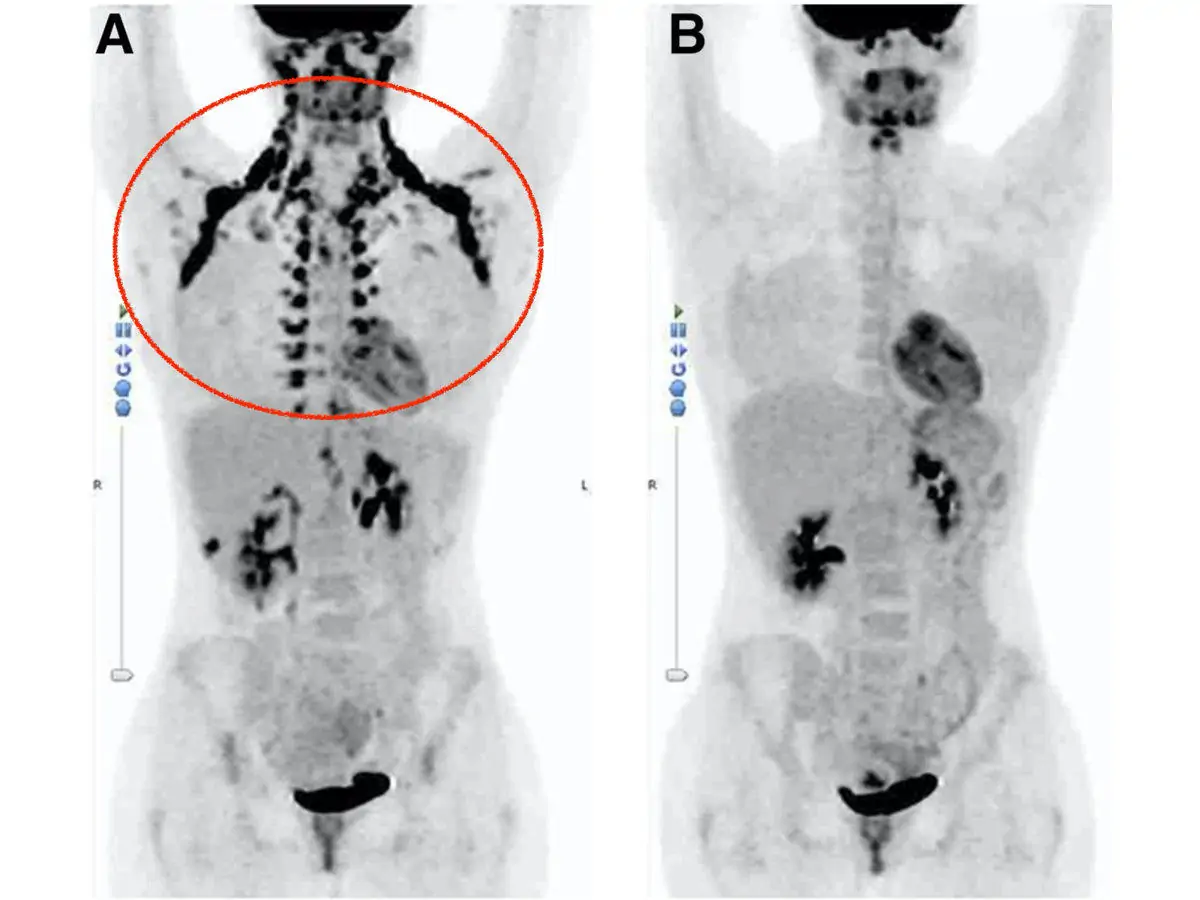

В красном круге на левом снимке, сделанном с помощью компьютерной томографии, видны области буровой жировой ткани. Правый снимок сделан через некоторое время после истощения запасов БЖТ